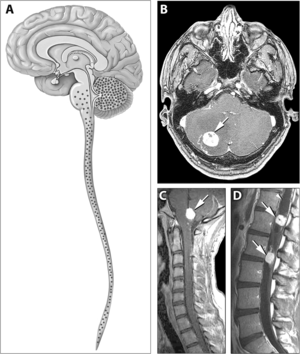

| Typical distribution of hemangioblastomas in von Hippel–Lindau disease. | |

Signs and symptoms associated with VHL disease include headaches, problems with balance and walking, dizziness, weakness of the limbs, vision problems, and high blood pressure. Conditions associated with VHL disease include angiomatosis, hemangioblastomas, pheochromocytoma, renal cell carcinoma, pancreatic cysts (pancreatic serous cystadenoma), endolymphatic sac tumor, and bilateral papillary cystadenomas of the epididymis (men) or broad ligament of the uterus (women).[5][6] Angiomatosis occurs in 37.2% of patients presenting with VHL disease and usually occurs in the retina. As a result, loss of vision is very common. However, other organs can be affected: strokes, heart attacks, and cardiovascular disease are common additional symptoms.[3] Approximately 40% of VHL disease presents with CNS hemangioblastomas and they are present in around 60-80%. Spinal hemangioblastomas are found in 13-59% of VHL disease and are specific because 80% are found in VHL disease.[7][8] Although all of these tumours are common in VHL disease, around half of cases present with only one tumour type.[8]